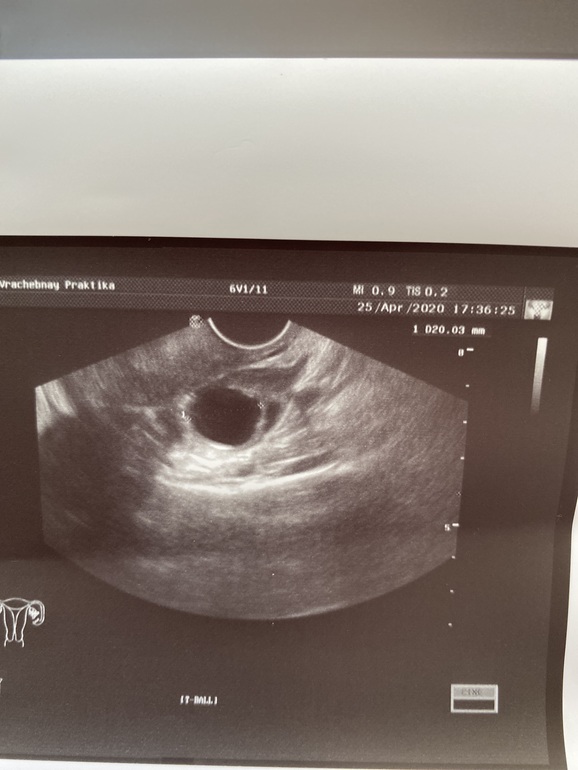

Желтое тело на УЗИ

Желтое тело можно обнаружить во время диагностической процедуры, если УЗИ пришлось на период сразу после овуляции. Это подтверждает, что цикл овуляторный и сама овуляция прошла нормально.

Желтое тело можно увидеть на трансабдоминальном и трансвагинальном УЗИ органов малого таза. Для женщин, живущих половой жизнью, более точным вариантом будет трансвагинальное исследование.

На экране аппарата врач УЗИ увидит неоднородное округлое образование. Появляется желтое тело в правом или левом яичнике в зависимости от локализации созревания доминантного фолликула и овуляторной яйцеклетки. Сторона созревания не имеет принципиального значения для будущей беременности и здоровья женщины.